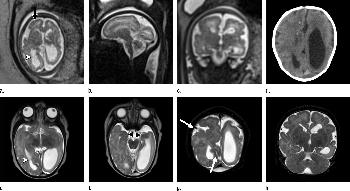

Figure 4. Images obtained in the case of an 18-year-old woman, first seen for rash at 10 weeks of pregnancy, with confirmed Zika virus infection. US findings obtained at 20 weeks of gestational age were reportedly normal, with normal head circumference of 17.5 cm. At 37 weeks of gestational age, (a) sagittal transvaginal and (b) coronal transabdominal US images obtained with the head upside down show a small head circumference (26.4 cm, corresponding to 28 weeks 5 days, below the 3rd percentile), moderate ventriculomegaly with dense intracranial calcifications (arrowheads on a), and abnormal head shape with flattened appearance and thickened skin (arrow on a). On the sonogram, it is difficult to precisely localize the calcifications, given the thin parenchyma. (c, d) Axial bone window CT images, (e) sagittal localizer CT image, and (f–h) axial CT images show microcephaly with cerebral atrophy, and, despite ventriculomegaly, the extra-axial cerebrospinal fluid spaces are still prominent. The hypoattenuating calcifications are predominantly located in the subcortical white matter at the gray matter–white matter interface. There is markedly abnormal skull shape with some eversion of the bones at the suture sites (particularly frontoparietal sites), with redundant skin folds (particularly in the parieto-occipital region). (i) Sagittal T1-weighted, (j, k) coronal T2-weighted, and (l) axial susceptibility-weighted MR images obtained at 1 month of age show an undersegmented midbrain, severe microcephaly, open sylvian fissures, and polymicrogyria. The dense calcifications are evident on the susceptibility-weighted image. On the sagittal images (a, e, i), note the small supratentorial compartment and associated skull deformity.

High-res (TIF) version

Figure 5. Images obtained in the case of a 33-year-old woman who had a rash at 10 weeks of pregnancy, with confirmed Zika virus infection. US performed at 19 weeks of gestational age showed a head circumference in the normal range (16.6 cm). (a, b) Sagittal and (c) coronal transvaginal US images obtained at the next US examination at 27 weeks 2 days of gestational age, however, showed the fetal head circumference to be 21.6 cm, which corresponded to 23 weeks 3 days (˂2.3 percentile, not shown). There was mild ven¬triculomegaly with septations in the occipital horns. Calcifications could be seen at the gray matter–white matter junction. The cerebrum was atrophic. There was blood clot in the region of the confluence of sinuses (arrow on c). (d) Coronal, (e) axial, and (f) sagittal T2- weighted fetal MR images obtained at 32 weeks show septations in the ventricles and an abnormal-appearing cortex, with a thickened and undersulcated cortex most marked on the left, compatible with polymicrogyria. The sagittal midline view shows microcephaly, blood clot in the region of the confluence of sinuses, and prominent skin folds. (g, h) Axial T2-weighted and (i) sagittal T1-weighted postnatal MR images obtained in the 4-week-old neonate show diffuse gyral abnormality and abnormal myelination. The septations in the ventri¬cles are again seen. The sagittal image shows thinning of the spinal cord at the craniocervical junction.

Figure 6. Images obtained in the case of a 24-year-old woman pregnant with twins, with characteristic rash at 9 weeks of pregnancy and confirmed Zika virus infection. (For each pair of images, the first image is of twin A, and the second image is of twin B.) At 14 weeks of gestational age, the fetal head size of both twins was normal. The head size never went below the 3rd percentile for either fetus in examinations at 19–28 weeks. (a, b) Sagittal and (c, d) axial fetal MR images were obtained at 36 weeks. (e, f) Axial and (g, h) surface reconstruction postnatal CT images and (i, j) axial T2-weighted and (k, l) coronal MR images were obtained 1 week after delivery at 38 weeks of gestational age. There is severe microcephaly with profound frontal lobe hypoplasia. Calcifications in the subcortical white matter at the gray matter–white matter junction are visualized. Both twins have a flattened appearance of the pons. The spinal cord is atrophic (best seen on a). Redundant skin is seen in the occipital region. There is polymicrogyria involving the frontal and parietal regions and atrophic cortex and white matter in the occipital regions. Each twin has hypoplasia of the corpus callosum, with prominent fornices. There is abnormal myelination in the occipital region that, in twin A (i), has the appearance of a cyst or septation within the ventricle. The cerebellum is somewhat small and nodular. There is lack of rotation of the hippocampi.